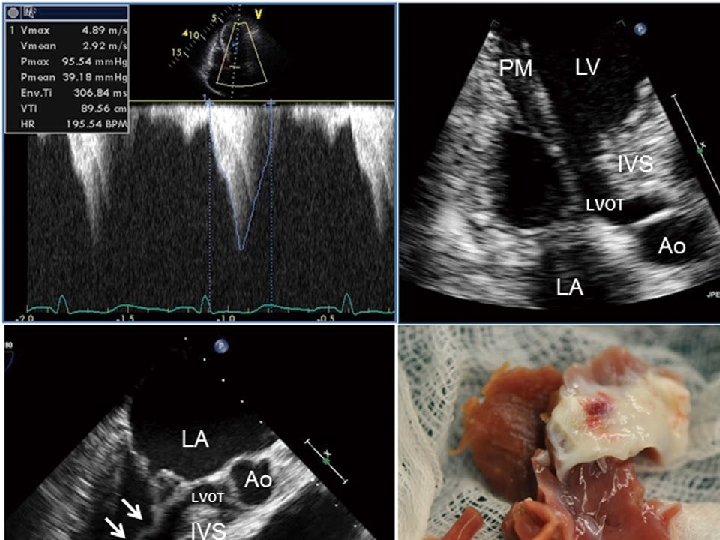

Explanations for the SAM of the mitral valve 1. Mitral valve is drawn toward the septum because of the lower pressure that occurs as blood is ejected at high velocity through a narrowed outflow tract (Venturi effect) 2. Mitral valve is pulled against the septum by contraction of the papillary muscles, which occurs because of the valve's abnormal location and septal hypertrophy altering the orientation of the papillary muscles 3. Hydrodynamic “drag” or the “pushing” force of flow

Elongated mitral leaflet causing SAM Christine Rodger British Heart Journal, 1976, 38, 732 -737.

Mitral regurgitation • Mitral regurgitation occurs in almost all patients with obstructive HCM as a consequence of SAM and abnormal mitral leaflet coaptation • Shah PM, Gramiak R, Kramer DH. Ultrasound localization of left ventricular outflow obstruction in hypertrophic obstructive cardiomyopathy. Circulation. 1969